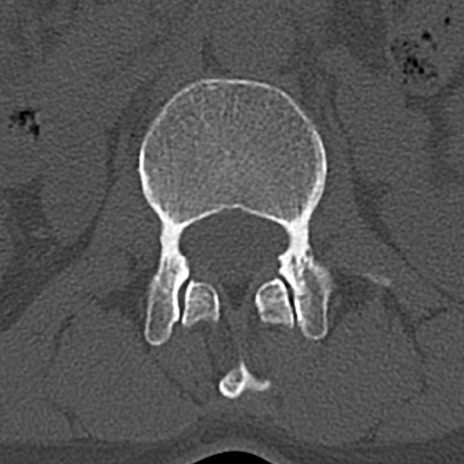

腰椎CT

横断像と矢状断像